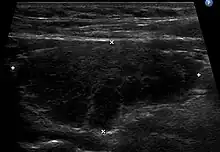

Échographie thyroïdienne en coupe longitudinale montrant un lobe thyroïdien augmenté de volume, hypoéchogène et hétérogène dans le cadre d'une thyroïdite de Hashimoto.

L'échographie de la thyroïde montre un goitre hypoéchogène[20],[18]. Le parenchyme thyroïdien devient plus hétérogène au cours de l'évolution. On peut notamment mettre en évidence des pseudo-nodules et des nodules de régénérations hyperéchogènes (white knight)[18]. Des ganglions récurrentiels peuvent être visualisés[18]. La vascularisation est hétérogène en Doppler couleur. L'étude en Doppler pulsé retrouve une élévation des vitesses systoliques[18], toutefois moindre que dans la maladie de Basedow.